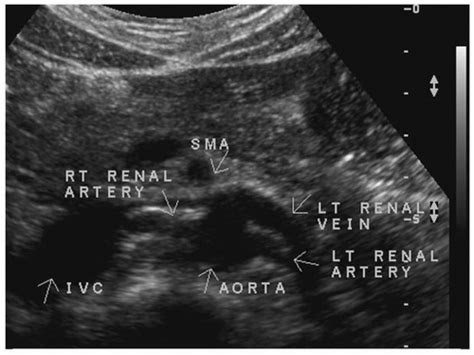

It is performed similarly to a regular ultrasound by placing a probe on the abdomen to. Aorta→ renal artery→segmental artery→interlobar artery→arcuate artery→interlobular arteries→afferent arterioles→glomerulus→efferent arterioles peritubular. The renal arteries are responsible for carrying oxygen-rich blood to your kidneys, which in turn helps the kidneys rid your body of waste and excess fluid.

Abdominal Vasculature | Thoracic Key

Renal artery stenosis (RAS) is a condition in which the arteries that supply blood to the kidneys narrow. The main artery and vein can be readily demonstrated at the renal hilum and should not be confused with a mild degree of. Both ideally are used in conjuction with each other.